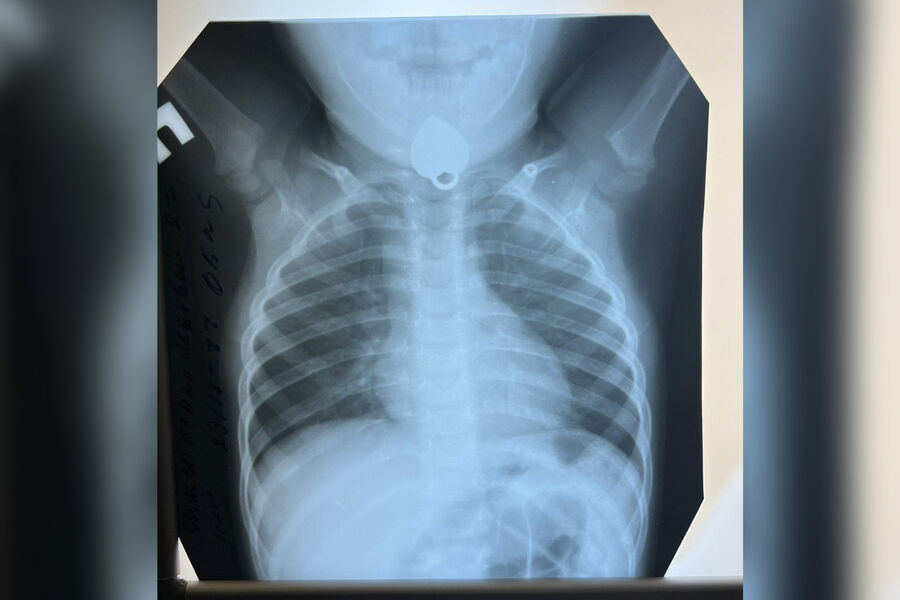

В Москве врачи извлекли из пищевода маленького пациента кулон. Об этом сообщает Telegram-канал Детской больницы №9 им. Г.Н. Сперанского.

Ребенок случайно проглотил кулон во время игры с украшением. Это заметили родители и отвезли его в больницу, где хирурги осмотрели ротовую полость. В преддверии пищевода медики обнаружили инородный предмет и извлекли его специальными щипцами.

Отмечается, что операция заняла всего несколько минут.

«К счастью, у маленького пациента не наблюдалось выраженных повреждений слизистой», — говорится в сообщении Telegram-канала больницы.